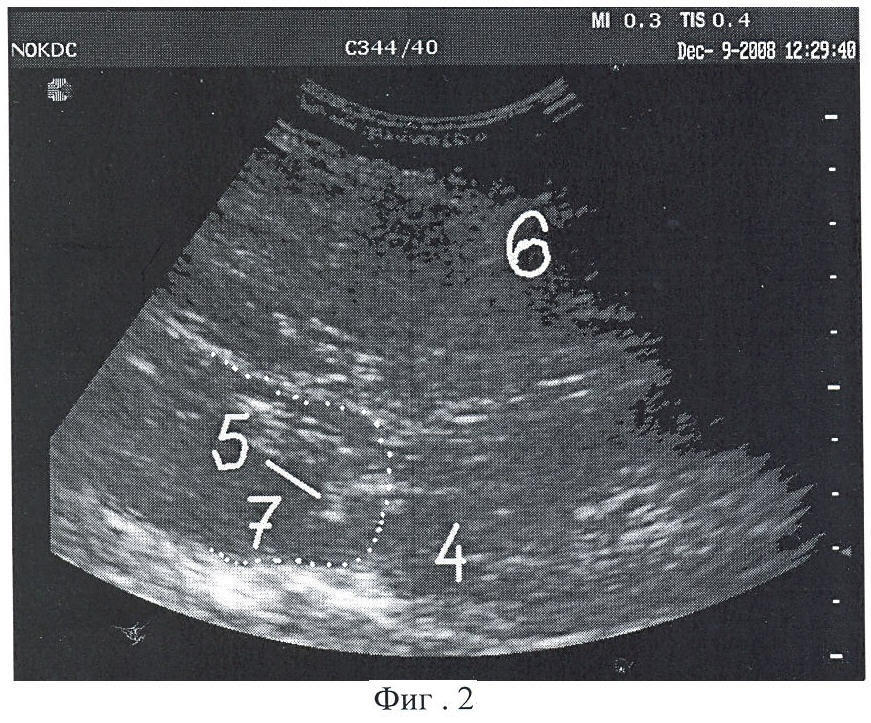

На фиг.2 - создание акустического окна у нижнего полюса почки (фаза выдоха, полюс сдвинут вверх). На фиг.3 изображено подведение биопсийной иглы к полюсу почки через акустическое окно (фаза глубокого вдоха, полюс почки под анэхогенным инфильтратом).

На фиг 2 обозначено:

4 - полюс почки;

5 - острие инъекционной иглы в акустическом окне;

6 - тело инъекционной иглы;

7 - искусственно созданное акустическое окно.